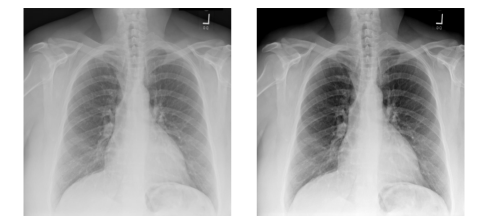

For our diagnostic application, we propose to explicitly avoid altering the image appearance using one of these methods. Instead, we propose an efficient method for dynamically windowing each image, i.e., adjust the brightness and contrast via a linear transformation of the image intensities. Given an arbitrary chest X-ray image 𝐈𝐈\mathbf{I}, let us denote its pixel value histogram function as h(x;𝐈)𝑥𝐈h(x;\mathbf{I}). Using Gaussian smoothing and median filtering, one can significantly reduce the noise of hh (visible as, e.g., signal spikes due to black background or white text overlay) as well as account for long function tails that affect the windowing of the image. As such, based on the processed function hh, we determine two bounds blowsubscript𝑏𝑙𝑜𝑤b_{low}, and bhighsubscript𝑏𝑖𝑔b_{high} which represent a tight intensity window for image I. The normalization is applied as follows, 𝐈=(𝐈blow)/(bhighblow)𝐈𝐈subscript𝑏𝑙𝑜𝑤subscript𝑏𝑖𝑔subscript𝑏𝑙𝑜𝑤\mathbf{I}=(\mathbf{I}-b_{low})/(b_{high}-b_{low}). A visual example is shown in Figure 3.

Refer to caption

Figure 3: An original image of the dataset is displayed (left) where the described normalization technique is applied (right).